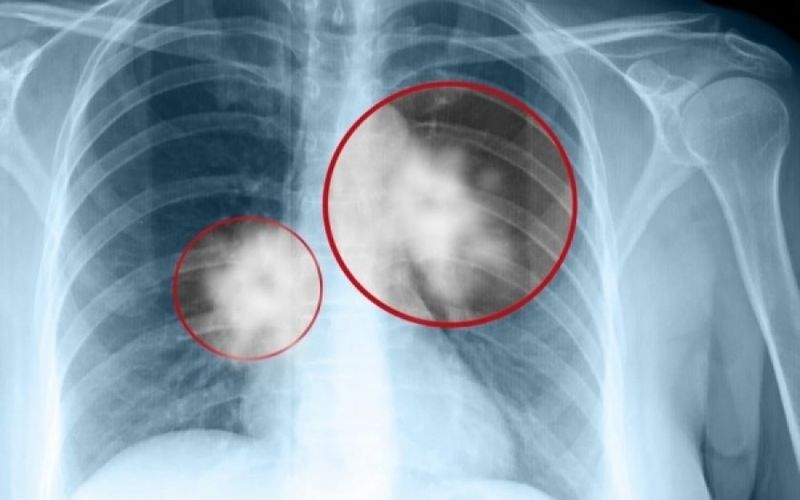

Καρκίνος του πνεύμονα: Πρόκειται για ένα συνηθισμένος και θανατηφόρο καρκίνο. Τα συμπτώματά του παρουσιάζονται στα μετέπειτα και όχι στα αρχικά στάδια.

Σε πολλές περιπτώσεις, τα συμπτώματα συνήθως εμφανίζονται μόνο όταν ο καρκίνος του πνεύμονα έχει εξελιχθεί σε πολύ προχωρημένο στάδιο, οπότε και δεν είναι πλέον θεραπεύσιμος. Όπως και πολλοί άλλοι καρκίνοι, ο καρκίνος του πνεύμονα μπορεί να ανιχνευθεί στο αρχικό στάδιο (στάδιο 1), οπότε είναι σημαντικό να αναγνωρίσουμε όλα τα συμπτώματα.